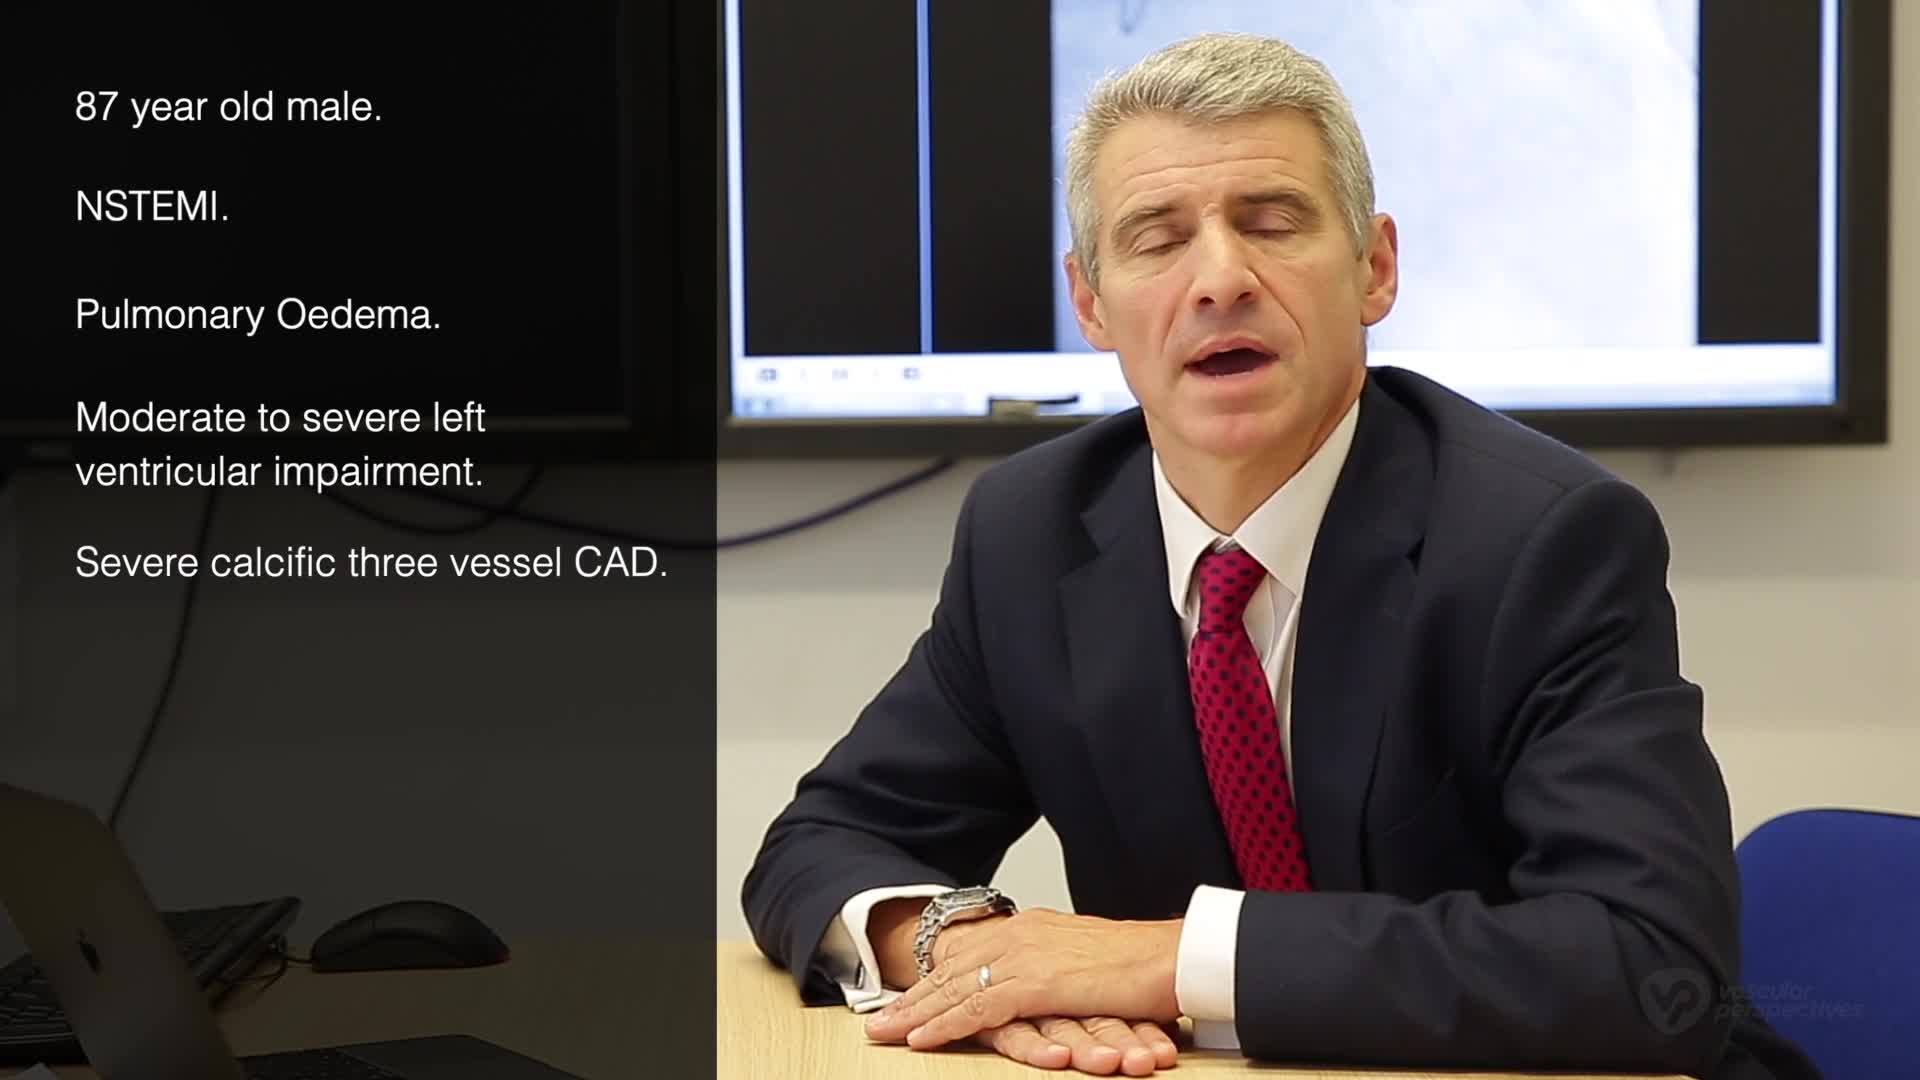

Intravascular Lithotripsy for Treatment of Severely Calcified Coronary Artery Disease: The Disrupt CAD III Study

Shockwave IVL Coronary Real-World Cases, Outcomes & Algorithms: An InCathLab Webinar